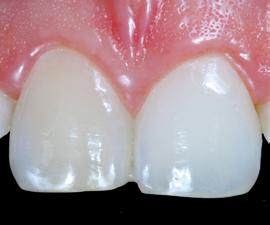

Restoring incisal wear and closing diastema with G-aenial A’CHORD. Courtesy of: Dr Aleksandra Slacan, Poland

Reshaping of teeth and diastema closure with G-aenial A’CHORD. Courtesy of: Dr Andres Silva, Spain